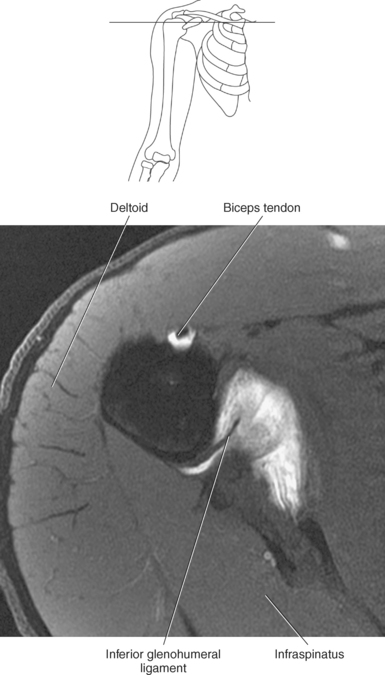

The edge of the glenoid fossa is surrounded by a fibrocartilaginous ring termed the glenoid labrum (glenoid lip) (Figure 9.17). The glenoid labrum is a fold of the articular capsule, which functions to deepen the articular surface of the glenoid fossa. Superiorly, the labrum blends with the long head of the biceps brachii muscle. In cross section it appears triangular (Figure 9.18). The three glenohumeral ligaments (superior middle, and inferior) are thickenings of the fibrous capsule that surrounds the shoulder joint; they contributes to the formation of the glenoid labrum (Figures 9.17 and 9.19). They extend from the supraglenoid tubercle of the scapula to the lesser tubercle of the humerus. Also aiding in strengthening the fibrous capsule is the coracohumeral ligament that passes from the lateral side of the coracoid process of the scapula to the anatomic neck of the humerus (Figure 9.19). The coracoacromial ligament is another important ligament located on the anterior portion of the shoulder. As this ligament joins the coracoid process and acromion, it forms a strong bridge, termed the coracoacromial arch, which protects the humeral head and rotator cuff tendons from direct trauma and prevents displacement of the humeral head superiorly (Figures 9.17 and 9.19). The coracoclavicular ligaments help to maintain the position of the clavicle, in relation to the acromion, by spanning the distance between the clavicle and coracoid process of the scapula (Figure 9.19). The acromioclavicular ligament, at the acromioclavicular joint, provides support for the superior surface of the shoulder (Figures 9.17 and 9.19). The transverse humeral ligament is a broad band of connective tissue passing from the greater tubercle to the lesser tubercle of the humerus, forming a bridge over the intertubercular groove for protection of the long head of the biceps tendon (Figure 9.19). The ligaments of the shoulder are demonstrated in Figures 9.20 through 9.30.